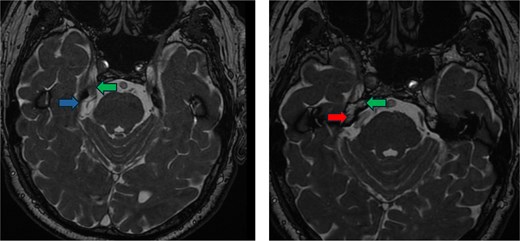

A 78-year-old male presented with 3 weeks of severe lancinating pain radiating into the right side of his face and jaw. The pain distribution matched the innervation pattern of the third branch of the trigeminal nerve. These episodes occurred 25–30 times per day, were short-lived, and were rated as severely painful with associated paresthesias. He was started on carbamazepine based on clinical suspicion for trigeminal neuralgia. A noncontrast MRI of the brain with fast imaging employing steady-state acquisition (FIESTA) sequence [9] showed a dolichoectatic, high-riding, and eccentric right vertebral artery compressing the inferior trigeminal nerve (Fig. 1). The decision was made to take the patient for MVD of the trigeminal nerve.

Preoperative imaging. FIESTA scan demonstrating the compression of the trigeminal nerve (green arrow) by the vertebral artery (red arrow) inferiorly and the superior cerebellar artery (blue arrow) superiorly.